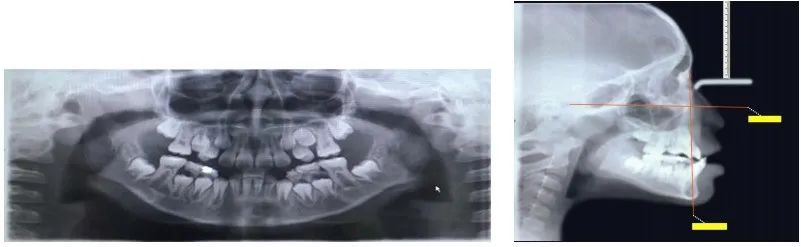

比如说这个孩子初诊时为替牙期,前牙对刃,但是患者家长拒绝接受矫正干预,一年半后复诊,前牙反颌重,并出现下颌前突。

首先要观察下颌骨形态。如果是高角,这种反颌难做,需要很多时间。如果是均角或者低角,矫治效果好而且稳定,不容易复发。

如果是上颌后缩,这种反颌也相对好做一些。但是如果是下颌前突,这种情况很差,下颌骨可能会随着生长越来越前突,反颌可能会加重。

替牙期结束之后,进入年轻恒牙列阶段,此时若是前牙反颌,可以使用上颌带环式的RPE快扩配合前方牵引。RPE快扩能够激活上颌骨的邻接骨缝,促进上颌骨前移。

年轻恒牙列阶段,正处于生长发育的高峰期,此时重要的是要与家长沟通,说明按时佩戴矫治器的重要性,以及下颌可能会随着全身生长而加速生长。1、年纪越小,前方牵引的效果越好。毕竟年纪越小,上颌骨骨缝尚未完全骨化闭合。一般10岁以下,可以更多地期待上颌骨A点前移,10岁以上可能更多的是上前牙唇倾。